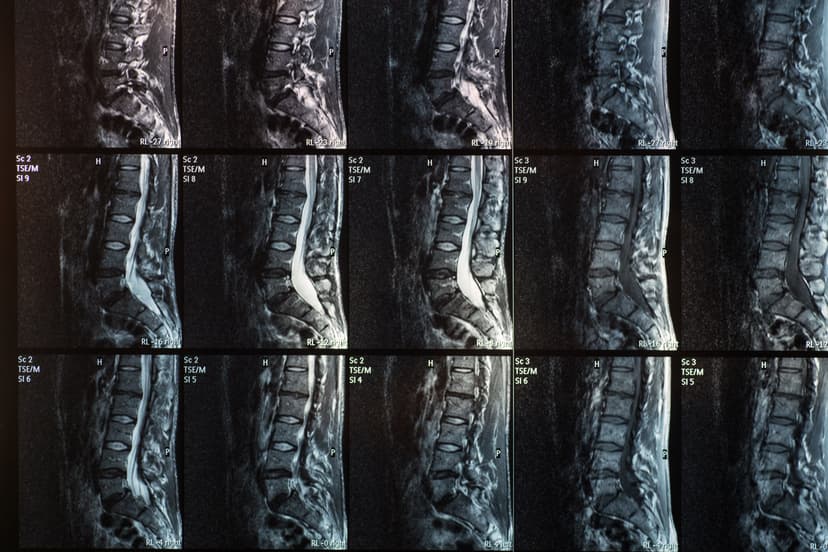

Marshall Deltoff DC, DACBR, FCCR(C) graduated with honors from the Canadian Memorial Chiropractic College in Toronto. He has over 30 years of academic, clinical and regulatory experience, having performed and read over 140,000 plain film x-ray examinations. He is the co-author of The Portable Skeletal X-Ray Library, a textbook of radiological bone diseases, as well as several book chapters, manuscripts and research papers and was selected to assist Yochum, T. & Rowe, L. in the final editorial process of textbook: “Essentials of Skeletal Radiology”. Dr. Deltoff has served as the President of the College of Chiropractors of Ontario, the regulatory body for over 5,000 DCs in that province. Currently, he is Professor of Radiology at Barcelona College of Chiropractic, and manages Images Radiology Consultants, an online x-ray reporting service for colleagues worldwide.